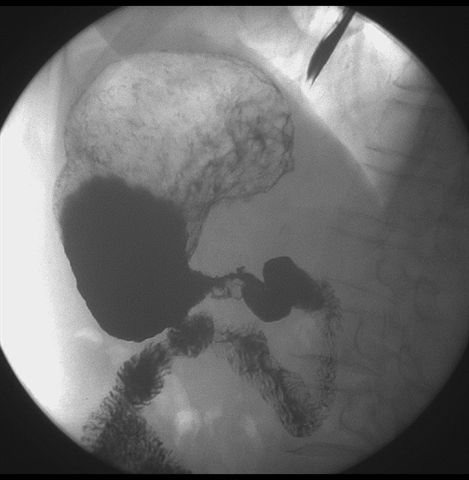

标题: X6872:F,69y,胃部不适。

胃窦至幽门段胃壁僵硬,扩张受限,局部纠集粘破坏,呈杵状。提示溃疡癌变可能性大。

胃窦癌可能性大,建议胃镜活检。钡剂太稀,吃的有点多。

支持考虑胃窦癌可能,胃内滞留液太多,胃窦部僵硬。

瀑布型胃,胃粘膜那是一个乱,窦部充盈不好,第16幅窦部粘膜反倒又很顺,先定个胃炎胃窦炎胃窦癌待排之类,建议进一步作胃镜检查。

胃窦部见钡池影,局部粘膜紊乱,纠集呈杵状改变,胃壁扩张受限,胃窦癌可能性大,建议胃镜检查.

胃窦部管腔扩张度较差,形态略有改变,胃窦粘膜显示欠佳,胃窦部占位可能性大,结合胃镜活检。

北京肿瘤医院胃镜诊断皮革胃。